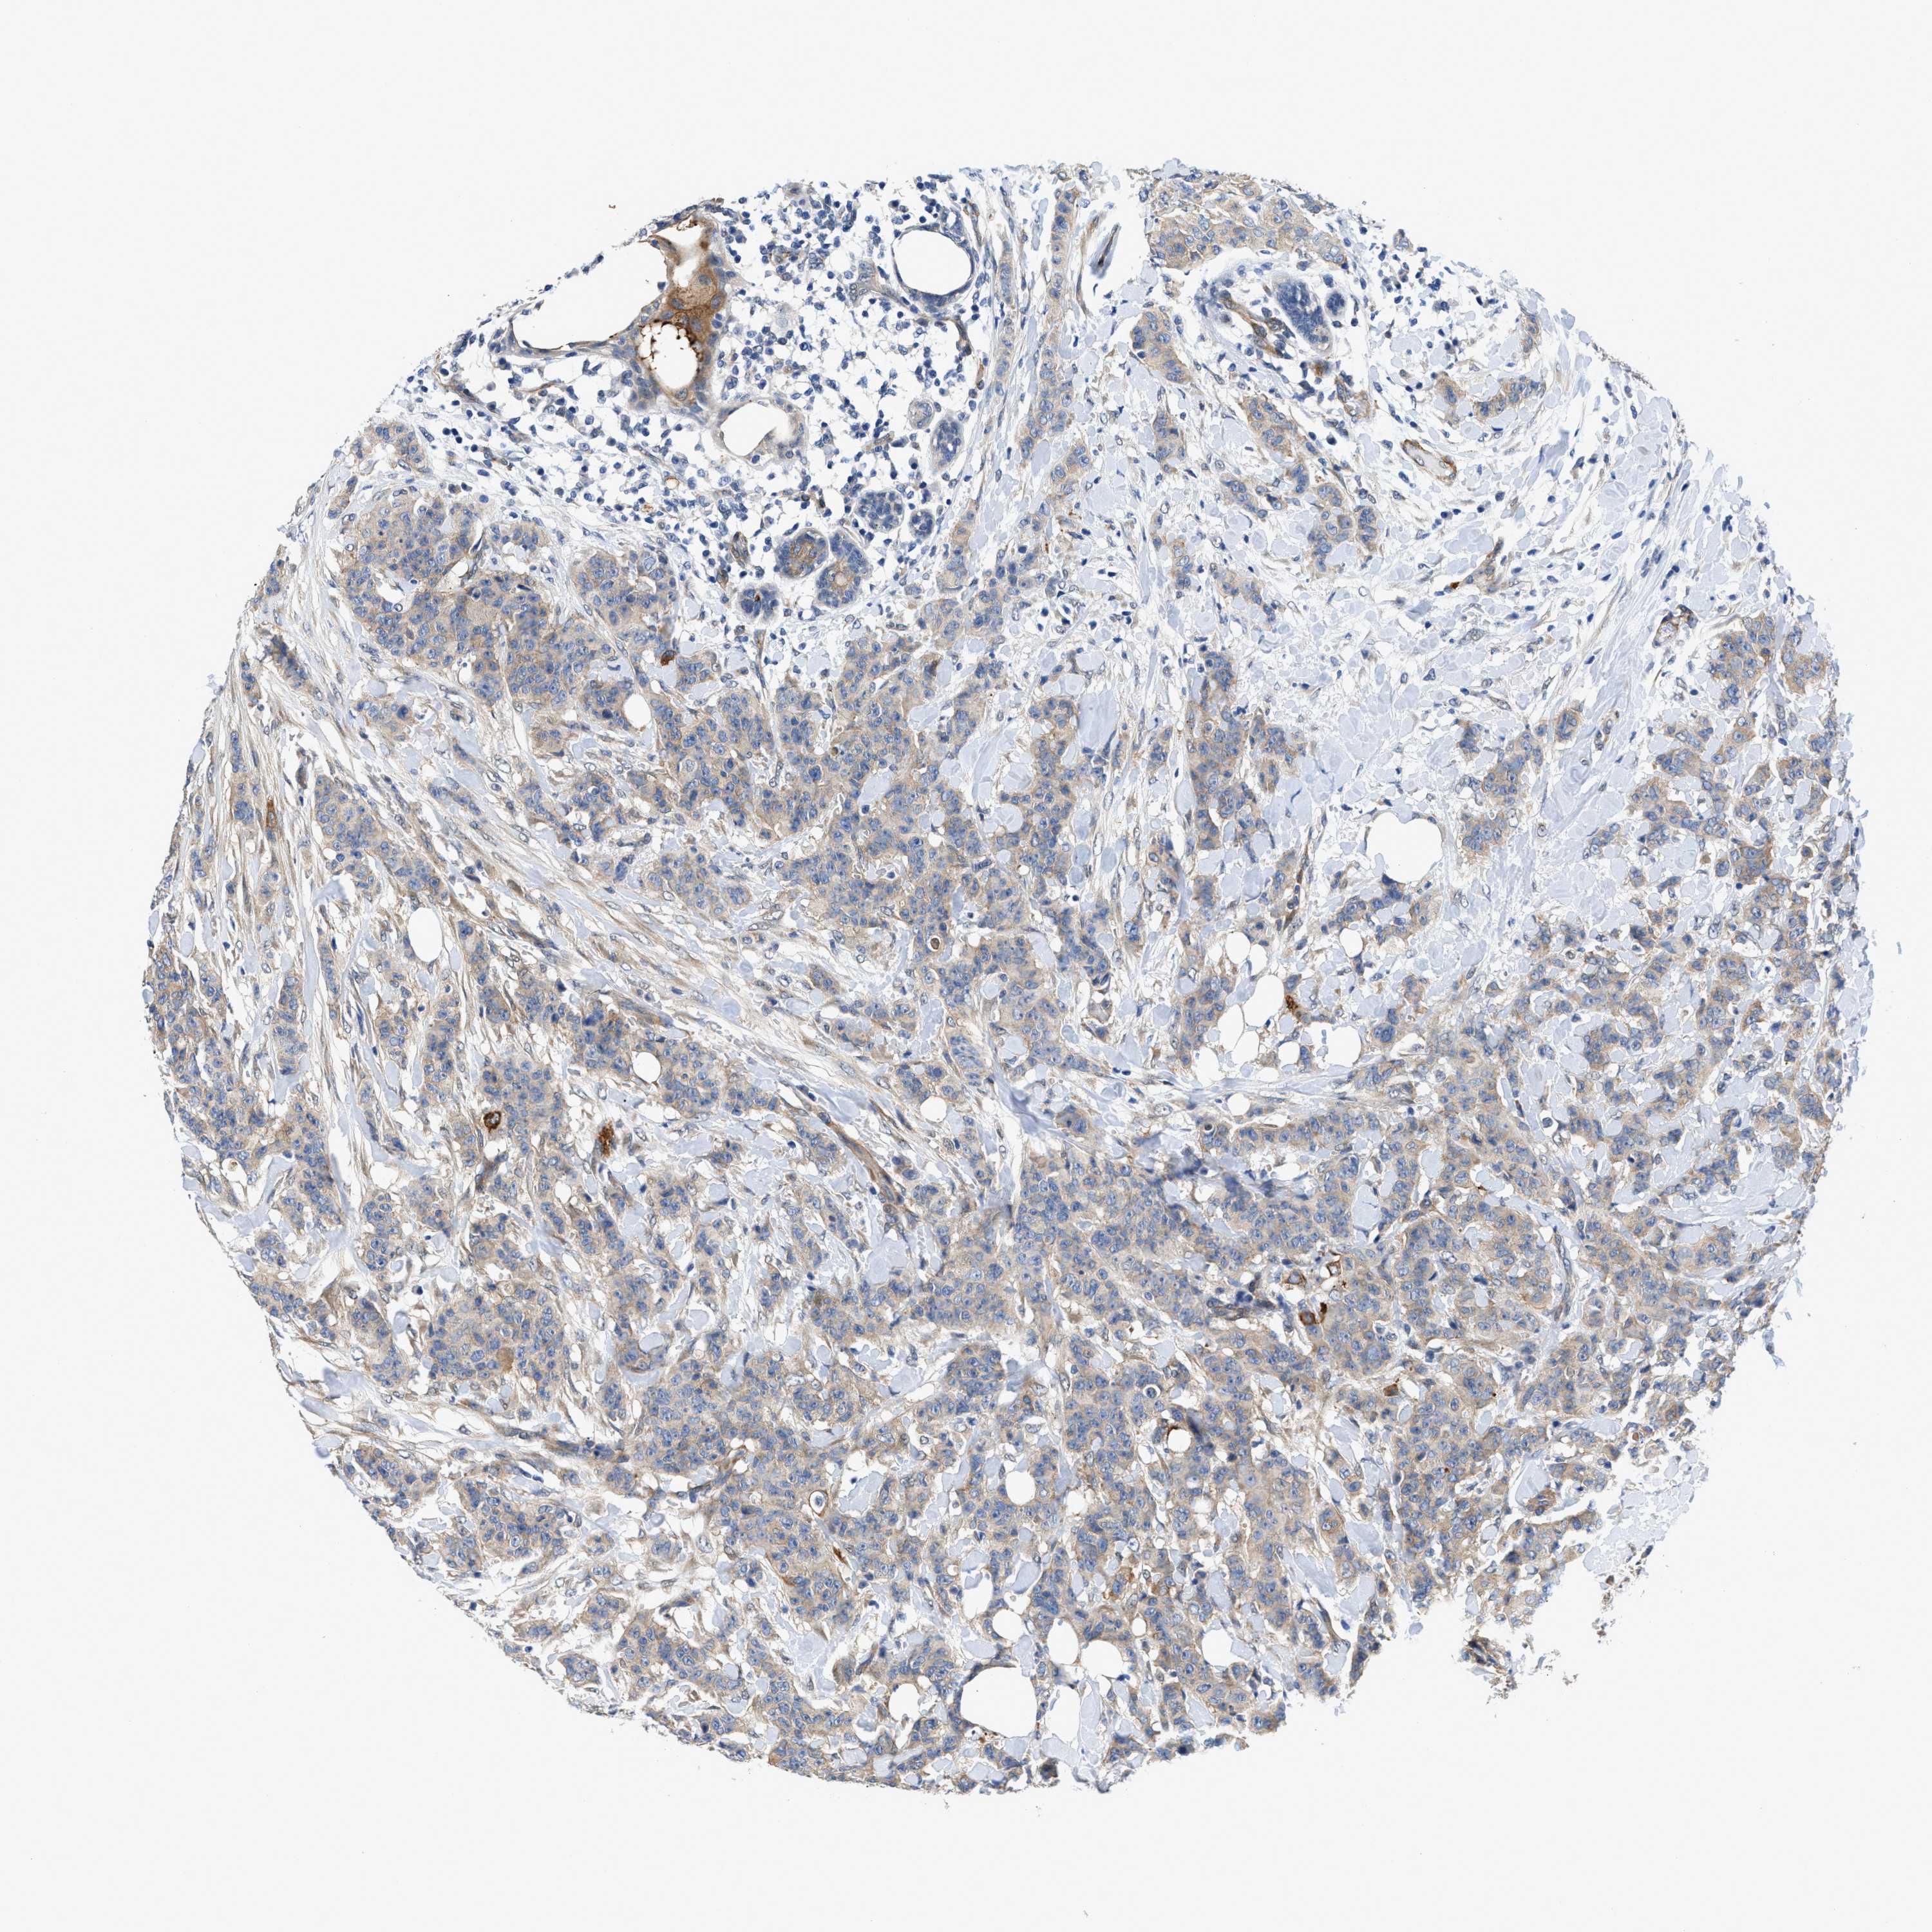

CANCER BREAST CANCER Show tissue menu

BRCA TCGA BRCA VALIDATION PROTEIN EXPRESSION